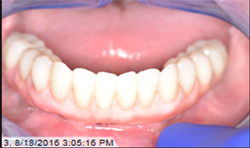

After normal healing and integration, 5 x 5 mm healing abutments with 2.5 mm wells were placed. At the impression appointment, the sulcus was prepared using a sulcus reamer and a PVS impression was taken and sent to the lab. The patient was happy with the wax try-in and the lab was instructed to finish the case. Delivery was uneventful (Figs. 5, 6).

Fig.5

Fig.6

At the one-month, post-op appointment the patient reported being able to eat corn on the cob and was happy with the fit and function of his hybrid, and the prosthesis continued to perform properly at subsequent follow-up visits.